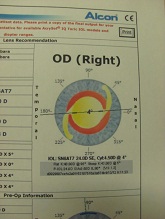

今日は水晶体亜脱臼による緑内障発作の患者様がいらっしゃり、お昼休みに緊急手術をさせて頂きました。